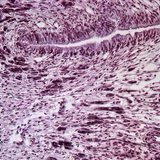

放大100倍

生物